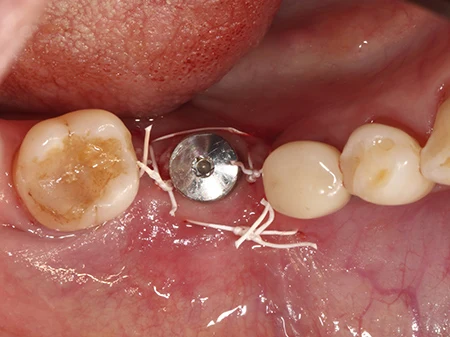

外側のインプラントのはみ出した部分に、人工の骨を移植していきます。

移植した骨に軟組織が入り込まないようにコラーゲンの膜で保護します。

キャップが歯ぐきから少しでた状態で縫合して終了です。骨の移植をした場合は2〜3ヶ月ほど待って型取りを行います。